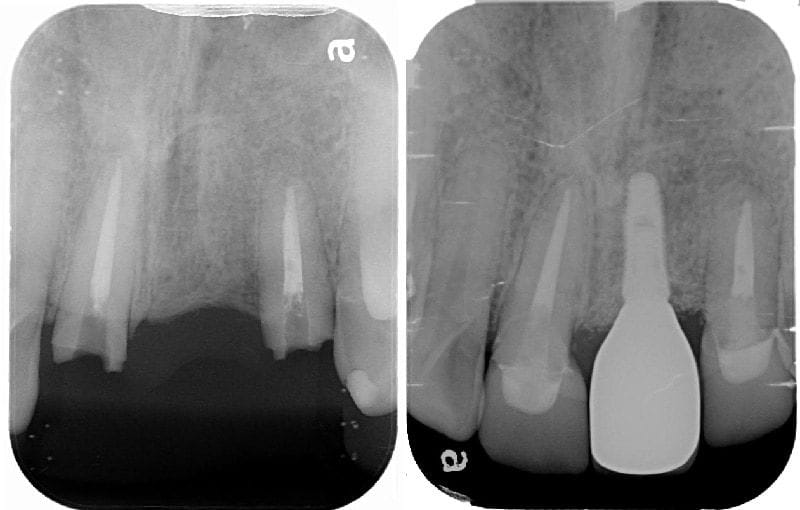

圖示:人工植牙手術前後X光片比較:(左)假牙拆除後,可見缺牙處兩邊的支柱牙結構破壞嚴重;(右)人工植牙手術後,完成全瓷冠假牙